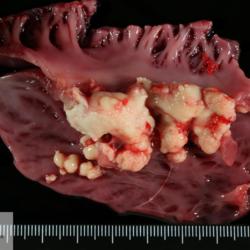

Pàgina anterior de 637 Pàgina següent 3181 total Porcine Specie: Porcine Organ: Heart Lesion: Endocarditis Lesion modifier: Endocarditis - Valvular Disease: - Position: 33 (7 views) Porcine Specie: Porcine Organ: Heart Lesion: Endocarditis Lesion modifier: Endocarditis - Valvular Disease: - Not viewed Canine Specie: Canine Organ: Intestine Lesion: Obstruction Lesion modifier: - Disease: - Files/Expedient: N-165/15 Position: 252 (1 views) Feline Specie: Feline Organ: Lung Lesion: Carcinoma Lesion modifier: Carcinoma - Adenocarcinoma Disease: - Files/Expedient: N-161/15 Position: 136 (2 views) Canine Specie: Canine Organ: Thoracic cavity Lesion: Atelectasis Lesion modifier: - Disease: - Files/Expedient: N-160/15 Not viewed Pàgina anterior de 637 Pàgina següent Títol Select...Avian (Exotic) (110)Avian (Poultry) (76)Bovine (317)Canine (935)Caprine (47)Equine (257)Feline (326)Ferret (19)General (127)Marine mammal (22)Non-human primate (20)Ovine (328)Porcine (379)Rabbit (61)Reptile (38)Rodent (28)Wildlife (91) Format Select...- (60)Abomasum (37)Adrenal gland (10)Blood (7)Blood vessel (50)Body as a whole (19)Bone (57)Bone marrow (21)Brain (93)Cloaca (1)Diaphragm (2)Ear (5)Esophagus (39)Eye (16)Fetus (12)Gallbladder (23)Gizzard (2)Heart (265)Intestine (356)Joint (32)Kidney (443)Larynx (5)Liver (326)Lung (264)Lymph node (91)Mammary gland (10)Mediastinum (1)Muscle (22)Nasal cavity (22)Nerve (7)Omasum (5)Oral cavity (63)Ovary (14)Oviduct (8)Pancreas (7)Parathyroid (5)Penis (10)Peritoneum (65)Pharynx (9)Pituitary gland (6)Placenta (7)Prostate (8)Proventriculus (3)Reticulum (1)Rumen (28)Sinus (7)Skin (181)Spinal cord (15)Spleen (105)Stomach (125)Teeth (1)Testicle (11)Thoracic cavity (31)Thymus (13)Thyroid gland (5)Tongue (32)Tonsils (11)Trachea (11)Urethra (5)Urinay bladder (61)Uterus (27)Vagina (1)Vulva (1)Yolk sac (1) Cobertura Select...- (152)Abomasitis (26)Abscess (27)Acidosis (1)Adenocarcinoma (20)Adenoma (9)Aerosacculitis (6)Agenesis (1)Agnathia (1)Alopecia (7)Amyloidosis (12)Aneurysm (6)Angiectasis (1)Anthracosis (1)Arteritis (11)Arthritis (15)Arthrogryposis (6)Artifact (4)Ascites (13)Atelectasis (8)Atherosclerosis (5)Atresia (1)Atrial septal defect (2)Atrophy (10)Autolysis (7)Bronchitis (6)Bronchopneumonia (26)Cachexia (2)Carcinoma (103)Cardiomyopathy (19)Cellulitis (2)Chemodectoma (4)Cholangiohepatitis (4)Cholangitis (19)Cholecystitis (4)Cholestasis (5)Chondrodysplasia (2)Chondrosarcoma (2)Chronic passive congestion (13)Chylothorax (2)Cirrhosis (6)Coelomitis (3)Coenurus cerebralis (4)Colitis (40)Congestion (17)Conjunctivitis (5)Coronitis (3)Cryptorchidism (3)Cyst (25)Cystitis (24)Dermatitis (69)Diaphragmatic hernia (4)Dilation (28)Discospondylitis (1)Disseminated intravascular coagulation (7)Dyschondroplasia (1)Dysplasia (29)Ectopia cordis (1)Ectopic ureter (1)Edema (55)Emphysema (5)Encephalitis (5)Endocardiosis (14)Endocarditis (26)Endometritis (5)Enteritis (118)Enterolith (6)Epulis (3)Esophagitis (14)Fasciitis (1)Fibrosis (7)Fibrous osteodystrophy (8)Fistula (1)Folliculitis (3)Fracture (2)Gastritis (34)Gingivitis (5)Glioma (8)Glomerulonephritis (21)Glossitis (25)Glycogenosis (1)Gout (8)Granuloma (2)Granulosa cell tumor (4)Hemangioma (9)Hemangiosarcoma (46)Hematoma (8)Hemoglobinuria (2)Hemopericardium (12)Hemoperitoneum (2)Hemorrhage (100)Hemosiderosis (7)Hemothorax (2)Hepatitis (78)Hernia (11)Histiocytosis (3)Hydatid cyst (11)Hydrocephalus (9)Hydrometra (1)Hydronephrosis (22)Hydropericardium (6)Hydrothorax (3)Hydroureter (5)Hyperkeratosis (8)Hyperostosis (4)Hyperplasia (37)Hypertrophy (9)Hypopigmentation (1)Hypoplasia (7)Hypopyon (1)Impaction (6)Infarction (63)Insulinoma (6)Intussusception (5)Jaundice (17)Laminitis (2)Laryngitis (2)Leiomyoma (5)Leukemia (13)Lipidosis (36)Lipoma (7)Lymphadenitis (45)Lymphadenopathy (7)Lymphangiectasia (6)Lymphangitis (5)Lymphoma (221)Malacia (11)Malignant melanoma (15)Mast cell tumor (11)Mastitis (8)Megaesophagus (2)Melanosis (3)Melena (4)Meningioma (6)Meningitis (6)Meningocele (2)Meningoencephalitis (5)Mesothelioma (5)Methemoglobinemia (2)Mineralization (10)Mucocele (5)Mucometra (1)Multilobular bone tumor (1)Mummification (3)Myelofibrosis (1)Myocarditis (4)Myositis (5)Necrosis (81)Nephritis (113)Nephroblastoma (6)Nephrosclerosis (1)Nephrosis (14)Neuritis (1)Obstruction (13)Omasitis (4)Omphalitis (1)Omphalophlebitis (7)Orchitis (4)Osteoarthrosis (5)Osteomyelitis (9)Otitis (2)Palatoschisis (3)Pancreatitis (3)Panniculitis (3)Papilloma (7)Parakeratosis (14)Patent ductus arteriosus (6)Peliosis hepatis (1)Perforation (17)Pericarditis (35)Peritonitis (39)Persistent right aortic arch (1)Pharyngitis (2)Pheochromocytoma (2)Phlebitis (2)Placentitis (6)Pleuritis (21)Pleuropneumonia (24)Pneumonia (109)Pneumothorax (3)Polycystosis (14)Polyp (5)Polyserositis (6)Posthitis (1)Proctitis (4)Prolapse (3)Prostatitis (3)Proventriculitis (1)Pyelonephritis (24)Pyometra (6)Pyothorax (4)Rhinitis (11)Rumenitis (6)Rupture (24)Salpingitis (3)Sarcoma (57)Sclerosis (1)Scoliosis (2)Seminoma (2)Sequestrum (2)Serous atrophy (14)Sinusitis (7)Splenitis (14)Splenomegaly (9)Spondylitis (6)Spondylosis (1)Stenosis (9)Stomatitis (32)Tenosynovitis (2)Teratoma (3)Thricobezoar (2)Thrombosis (16)Tonsilitis (4)Torsion (13)Tracheitis (4)Tympany (7)Typhlitis (8)Typhlocolitis (4)Ulcer (43)Urethritis (1)Urolithiasis (36)Uroperitoneum (1)Uveitis (1)Vasculitis (15)Ventricular septal defect (3)Volvulus (11) Matèria Select... - (14)- (1653)- (152)Abomasitis - Catarrhal (2)Abomasitis - Catarrhal-hemorrhagic (1)Abomasitis - Chronic (1)Abomasitis - Fibrinous-necrotizing (2)Abomasitis - Hyperplasic (5)Abomasitis - Hyperplasic - Chronic (1)Abomasitis - Necrotic (1)Abomasitis - Necrotizing (2)Abomasitis - Ulcerative (5)Adenocarcinoma (9)Aerosacculitis - Granulomatous (1)Amyloidosis - Chronic (1)Arteritis - Necrotic (2)Arteritis - Necrotizing (1)Arthritis - Chronic (4)Arthritis - Fibrinous-purulent (3)Arthritis - Serous (4)Arthritis - Subacute (1)Ascites - Serous (1)Atrophy - Serous (1)Bronchitis - Catarrhal (3)Bronchitis - Suppurative (1)Bronchopneumonia - Catarrhal-purulent (17)Bronchopneumonia - Fibrinous (1)Bronchopneumonia - Granulomatous (1)Bronchopneumonia - Purulent (1)Bronchopneumonia - Suppurative (5)Carcinoma - Adenocarcinoma (33)Carcinoma - Adenocarcinoma - Hepatocellular (2)Carcinoma - Adenocarcinoma - Mucinous (1)Carcinoma - Basosquamous (1)Carcinoma - Cholangiocellular (3)Carcinoma - Hepatocellular (4)Carcinoma - Metastatic (3)Carcinoma - Squamous cell carcinoma (13)Carcinoma - Transitional cell (2)Cardiomyopathy - Dilated (13)Cardiomyopathy - Hypertrophic (6)Cellulitis - Necrotizing (1)Cholangitis - Chronic (8)Cholangitis - Hyperplasic (3)Cholecystitis - Fibrinous-necrotizing (1)Coelomitis - Fibrinous (1)Coelomitis - Granulomatous (1)Colitis - Catarrhal (3)Colitis - Catarrhal-hemorrhagic (1)Colitis - Fibrinous (1)Colitis - Fibrinous-necrotizing (1)Colitis - Fibrinous-necrotizing (Diphtheritic) (6)Colitis - Granulomatous (2)Colitis - Hemorrhagic (4)Colitis - Hemorrhagic-necrotizing (3)Colitis - Necrotizing (2)Colitis - Ulcerative (6)Congestion - Chronic (2)Conjunctivitis - Hyperplasic (1)Conjunctivitis - Purulent (3)Coronitis - Ulcerative (1)Cystitis - Chronic (3)Cystitis - Fibrinous (1)Cystitis - Fibrinous-necrotizing (1)Cystitis - Follicular (1)Cystitis - Hemorrhagic (6)Cystitis - Hemorrhagic-ulcerative (1)Cystitis - Necrotizing (9)Cystitis - Perforated (1)Dermatitis - Granulomatous (14)Dermatitis - Hyperkeratotic (10)Dermatitis - Hyperplasic (proliferative) (1)Dermatitis - Hyperplastic (10)Dermatitis - Necrotizing (4)Dermatitis - Pustular (4)Dermatitis - Ulcerative (2)Dilation - Chronic (1)Discospondylitis - Necrotizing (1)Dysplasia - Follicular (5)Edema - Interstitial (6)Emphysema - Interstitial (1)Encephalitis - Granulomatous (1)Encephalitis - Nonsuppurative (1)Endocardiosis - Mitral (7)Endocardiosis - Mitral - Chronic (5)Endocarditis - Valvular (6)Endocarditis - Valvular - Mitral (7)Endocarditis - Valvular - Pulmonic (1)Endocarditis - Valvular - Subacute (1)Endocarditis - Valvular - Subaortic (5)Endocarditis - Valvular - Tricuspid (4)Endometritis - Purulent (3)Endometritis - Purulent-hemorrhagic (2)Enteritis - Catarrhal (23)Enteritis - Catarrhal - Acute (1)Enteritis - Catarrhal-hemorrhagic (5)Enteritis - Catarrhal-hemorrhagic - Acute (2)Enteritis - Fibrinous (16)Enteritis - Fibrinous - Acute (3)Enteritis - Fibrinous-necrotizing (7)Enteritis - Granulomatous (14)Enteritis - Granulomatous - Chronic (1)Enteritis - Granulomatous - Multifocal (1)Enteritis - Hemorrhagic (17)Enteritis - Hemorrhagic - Acute (1)Enteritis - Hemorrhagic-necrotizing (1)Enteritis - Hyperplasic (proliferative) (4)Enteritis - Necrotizing (4)Enteritis - Necrotizing - Acute (1)Enteritis - Necrotizing - Hemorrhagic (1)Enteritis - Necrotizing-ulcerative (2)Enteritis - Ulcerative (1)Enteritis - Ulcerative-hemorrhagic (1)Esophagitis - Erosive-ulcerative (6)Esophagitis - Necrotizing (4)Esophagitis - Ulcerative (1)Esophagitis - Ulcerative-necrotizing (1)Fasciitis - Fibrinous-purulent (1)Folliculitis - Purulent (2)Gastritis - Catarrhal (2)Gastritis - Chronic (1)Gastritis - Follicular (1)Gastritis - Hemorrhagic (2)Gastritis - Hemorrhagic-necrotizing (1)Gastritis - Hypertrophic (2)Gastritis - Inclusion bodies (1)Gastritis - Mineralization (1)Gastritis - Mycotic (1)Gastritis - Necrotizing (2)Gastritis - Ulcerative (6)Gastritis - Uremic (3)Gingivitis - Erosive (2)Gingivitis - Hyperplasic (proliferative) (1)Gingivitis - Necrotizing (1)Glomerulonephritis - Chronic (7)Glomerulonephritis - Membranoproliferative (3)Glomerulonephritis - Membranoproliferative - Chronic (1)Glomerulonephritis - Membranous (3)Glomerulonephritis - Membranous - Chronic (1)Glomerulonephritis - Proliferative (2)Glomerulonephritis - Subacute (1)Glossitis - Erosive (2)Glossitis - Granulomatous (6)Glossitis - Hyperplasic (1)Glossitis - Hyperplasic (proliferative) (2)Glossitis - Hyperplastic (1)Glossitis - Necrotizing (2)Glossitis - Necrotizing - Focal (1)Glossitis - Ulcerative (6)Glossitis - Ulcerative - Multifocal (1)Glossitis - Ulcerative - Subacute (1)Glycogenosis (1)Granuloma - Eosinophilic (1)Hemangiosarcoma - Metastatic (2)Hemorrhage - Acute (1)Hemorrhage - Subcapsular (3)Hepatitis - Abscess (9)Hepatitis - Acute (3)Hepatitis - Chronic (4)Hepatitis - Chronic interstitial (6)Hepatitis - Granulomatous (7)Hepatitis - Interstitial - Multifocal (1)Hepatitis - Interstitial - Subacute (1)Hepatitis - Necrotizing (17)Hepatitis - Necrotizing - Acute (2)Hepatitis - Necrotizing - Hemorrhagic (1)Hepatitis - Necrotizing - Subacute (1)Hepatitis - Pyogranulomatous (7)Hepatitis - Subacute (4)Hydronephrosis - Chronic (1)Hydropericardium - Chronic (1)Hyperplasia - Erythroid (1)Hyperplasia - Lymphoid (3)Hyperplasia - Myeloid (1)Hyperplasia - Nodular (8)Hypertrophy - Concentric (2)Hypertrophy - Eccentric (3)Infarction - Acute (17)Infarction - Acute - Multifocal (2)Infarction - Chronic (5)Infarction - Chronic - Multifocal (1)Infarction - Subacute (18)Infarction - Subacute - Focal (2)Laminitis - Chronic (2)Laryngitis - Necrotic (1)Laryngitis - Necrotizing (1)Leukemia - Lymphoid leukemia (2)Leukemia - Non-lymphoid leukemia (6)Lipidosis - Multifocal (1)Lipidosis - Panlobular (1)Lipidosis - Panlobular - Generalized (2)Lymphadenitis - Granulomatous (24)Lymphadenitis - Granulomatous - Chronic (3)Lymphadenitis - Hemorrhagic (1)Lymphadenitis - Necrotizing (5)Lymphadenitis - Necrotizing (caseous) (11)Lymphangitis - Granulomatous (1)Lymphangitis - Purulent (1)Lymphangitis - Ulcerative (1)Lymphoma - Alimentary lymphoma (7)Lymphoma - Cutaneous lymphoma (6)Lymphoma - Lymphosarcoma (2)Lymphoma - Mediastinal lymphoma (1)Lymphoma - Multicentric lymphoma (29)Malignant melanoma - Malignant (1)Malignant melanoma - Metastatic (1)Mast cell tumor - Metastatic (1)Mastitis - Fibrinous-purulent (2)Mastitis - Necrotic (1)Mastitis - Purulent (3)Mastitis - Suppurative (1)Meningitis - Fibrinous-purulent (2)Meningitis - Purulent (4)Meningoencephalitis - Necrotizing (3)Meningoencephalitis - Nonsuppurative (2)Mineralization - Metastatic (4)Myocarditis - Fibrous - Chronic (1)Myocarditis - Granulomatous (1)Myositis - Purulent (2)Necrosis - Acute (1)Necrosis - Cortical (5)Necrosis - Follicular (1)Necrosis - Papillary (8)Necrosis - Papillary - Acute (3)Necrosis - Subacute (3)Necrosis - Tubular (6)Nephritis - Embolic (2)Nephritis - Embolic suppurative (7)Nephritis - Granulomatous (27)Nephritis - Granulomatous - Chronic (1)Nephritis - Granulomatous - Multifocal (1)Nephritis - Interstitial (6)Nephritis - Interstitial - Acute (4)Nephritis - Interstitial - Chronic (41)Nephritis - Interstitial - Subacute (12)Nephritis - Purulent (7)Nephritis - Purulent - Acute (2)Nephritis - Purulent - Multifocal (3)Nephrosis - Cholemic (3)Nephrosis - Hemoglobinuric (10)Omasitis - Fibrinous-necrotizing (1)Omasitis - Hyperkeratotic (1)Omasitis - Necrotizing (2)Omphalophlebitis - Fibrinous-purulent (2)Omphalophlebitis - Purulent (3)Orchitis - Necrotizing (1)Osteomyelitis - Necrotizing (7)Osteomyelitis - Purulent (2)Otitis - Necrotizing (1)Otitis - Proliferative (1)Pancreatitis - Acute (1)Pancreatitis - Chronic (1)Pancreatitis - Granulomatous (1)Panniculitis - Fibrinous-purulent (1)Panniculitis - Necrotic (1)Panniculitis - Parasitic (1)Perforation - Acute (2)Pericarditis - Fibrinous (19)Pericarditis - Fibrinous - Subacute (1)Pericarditis - Fibrinous-necrotizing (1)Pericarditis - Fibrinous-purulent (3)Pericarditis - Fibrous (1)Pericarditis - Fibrous - Chronic (1)Pericarditis - Gangrenous (6)Pericarditis - Granulomatous (1)Pericarditis - Granulomatous - Chronic (2)Peritonitis - Acute (1)Peritonitis - Fibrinous (11)Peritonitis - Fibrinous - Subacute (1)Peritonitis - Fibrinous-purulent (5)Peritonitis - Fibrous (3)Peritonitis - Granulomatous (6)Peritonitis - Purulent (1)Peritonitis - Purulent-hemorrhagic (1)Peritonitis - Pyogranulomatous (3)Pharyngitis - Fibrinous-necrotizing (1)Pharyngitis - Ulcerative (1)Pheochromocytoma - Metastatic (1)Phlebitis - Purulent (1)Placentitis - Fibrinous-necrotizing (1)Placentitis - Necrotic (1)Placentitis - Necrotizing (1)Pleuritis - Chronic (1)Pleuritis - Fibrinous (3)Pleuritis - Fibrinous-purulent (2)Pleuritis - Fibrous (2)Pleuritis - Granulomatous (3)Pleuritis - Hyperplastic (2)Pleuritis - Purulent (2)Pleuritis - Pyogranulomatous (1)Pleuropneumonia - Fibrinous (13)Pleuropneumonia - Fibrinous-necrotizing (5)Pleuropneumonia - Granulomatous (2)Pleuropneumonia - Hemorrhagic-necrotizing (4)Pneumonia - Aspiration (11)Pneumonia - Bronchointerstitial (4)Pneumonia - Bronchointerstitial - Subacute (1)Pneumonia - Embolic (5)Pneumonia - Granulomatous (37)Pneumonia - Granulomatous - Multifocal (4)Pneumonia - Hemorrhagic-necrotizing (2)Pneumonia - Interstitial (7)Pneumonia - Interstitial - Acute (8)Pneumonia - Interstitial - Chronic (6)Pneumonia - Interstitial - Subacute (15)Pneumonia - Necrotizing (2)Pneumonia - Pyogranulomatous (2)Pneumonia - Verminous (5)Polyserositis - Fibrinous (6)Polyserositis - Fibrous (1)Proctitis - Fibrinous-necrotizing (1)Proctitis - Parasitic (2)Prostatitis - Purulent (1)Pyelonephritis - Acute (2)Pyelonephritis - Chronic (3)Rhinitis - Catarrhal (2)Rhinitis - Fibrinous (1)Rhinitis - Granulomatous (4)Rhinitis - Purulent (3)Rumenitis - Acute (1)Rumenitis - Erosive (1)Rumenitis - Necrotizing (1)Rupture - Acute (3)Sarcoma - Fibrosarcoma (12)Sarcoma - Hemangiosarcoma (11)Sarcoma - Histiocytic (7)Sarcoma - Metastatic (1)Sarcoma - Multilobular tumor of bone (1)Sequestrum - Chronic (2)Sinusitis - Suppurative (1)Splenitis - Granulomatous (8)Splenitis - Granulomatous - Chronic (1)Splenitis - Necrotizing (3)Splenitis - Necrotizing (caseous) (2)Spondylitis - Necrotizing (2)Stenosis - Intestinal (1)Stenosis - Valvular - Subaortic (4)Stomatitis - Erosive (12)Stomatitis - Erosive-ulcerative (3)Stomatitis - Fibrinous-necrotizing (1)Stomatitis - Fibrinous-necrotizing (Diphtheritic) (1)Stomatitis - Granulomatous (1)Stomatitis - Hyperplasic (1)Stomatitis - Hyperplasic (proliferative) (1)Stomatitis - Necrotizing (2)Stomatitis - Ulcerative (5)Stomatitis - Ulcerative - Multifocal (1)Stomatitis - Ulcerative-necrotizing (1)Tonsilitis - Necrotizing (4)Torsion - Acute passive hyperemia (5)Tracheitis - Catarrhal (3)Tracheitis - Fibrinous (1)Tracheitis - Granulomatous (1)Typhlitis - Catarrhal (1)Typhlitis - Fibrinous-necrotizing (2)Typhlitis - Hemorrhagic (2)Typhlitis - Ulcerative-hemorrhagic (1)Typhlocolitis - Fibrinous-necrotizing (2)Typhlocolitis - Proliferative (1)Ulcer - Chronic (6)Ulcer - Multifocal (2)Ulcer - Mycotic (1)Ulcer - Perforated (6)Urethritis - Hemorrhagic (1)Urolithiasis - Chronic (2)Uveitis - Granulomatous (1)Vasculitis - Granulomatous (1)Vasculitis - Necrotizing (1) Editor Select...- (1970)Acidosis (2)Actinobacillosis (Pleuropneumonia) (11)Aelurostrongylosis (2)African horse sickness (13)African swine fever (14)Alopecia X (1)Anaplasmosis (4)Anthrax (2)Aortic thromboembolism (feline) (7)Ascariasis (15)Aspergillosis (18)Atopic dermatitis (1)Atrophic rhinitis (3)Babesiosis (6)Blackhead (1)Bluetongue (11)Border disease (2)Bovine viral diarrhea (21)Brucellosis (2)Candidiasis (5)Canine distemper (14)Caprine arthritis-encephalitis (2)Capture myopathy (1)Cardiac insufficiency (17)Caseous lymphadenitis (7)Chlamydiosis (2)Classical swine fever (19)Clostridiosis (19)Coccidiosis (9)Coenurosis (4)Colibacillosis (21)Contagious ecthyma (7)Copper toxicosis (11)Cowdriosis (Heartwater) (3)Cryptococcosis (3)Cryptosporidiosis (2)Cysticercosis (23)Demodicosis (1)Diabetes (1)Dicrocoeliosis (5)Dictyocaulosis (4)Dirofilariasis (7)Discoid lupus erythematosus (3)Echinococcosis (17)Edema disease (7)Egg drop syndrome (1)Encephalitozoonosis (5)Enterotoxemia (1)Enzootic bovine leukosis (46)Epitheliogenesis imperfecta (3)Equine rhinopneumonitis (2)Equine verminous arteritis (strongylosis) (7)Erysipelas (5)Exudative epidermitis (7)Fasciolasis (11)Feline eosinophilic dermatoses (1)Feline hepatic lipidosis (8)Feline histiocytosis (4)Feline infectious peritonitis (38)Feline leukemia (4)Feline lower urinary tract disease (3)Feline panleukopenia (16)Feline viral rhinotracheitis (1)Flea allergy dermatitis (1)Foot and mouth disease (2)Gasterophilosis (4)Glasser's disease (15)Gousiekte (4)Gout (6)Haemonchosis (9)Hemolytic anemia (4)Hemorrhagic diathesis (1)Hepatic insufficiency (11)Hepatosis dietetica (7)Herpesvirosis (6)Hyperadrenocorticism (7)Hyperparathyroidism (10)Hypertrophic osteopathy (6)Hypervitaminosis D (1)Hypodermosis (1)Inclusion body hepatitis (4)Infectious bovine rhinotracheitis (5)Infectious bronchitis (5)Infectious canine hepatitis (13)Influenza (4)Juvenile nephropathy (8)Lamb dysentery (4)Leishmaniasis (28)Leptospirosis (1)Leukosis (5)Listeriosis (4)Lumpy skin disease (3)Maedi-visna (4)Malignant catarrhal fever (12)Mange (6)Mannheimiosis (5)Marek's disease (7)Metabolic bone disease (2)Mucoid enteropathy (5)Mulberry heart disease (5)Myasis (1)Mycobacteriosis (22)Mycosis fungoides (6)Myxomatosis (3)Necrobacillosis (5)Neonatal isoerythrolysis (6)Nocardiosis (4)Oestrosis (2)Onchocerciasis (1)Osteochondrosis (1)Ostertagiosis (6)Ovine pulmonary adenocarcinoma (5)Oxyuriasis (1)Pacheco's disease (4)Papillomatosis (6)Paratuberculosis (18)Parvovirosis (17)Pasteurellosis (11)Pemphigus foliaceus (1)Periodontal disease (1)Polioencephalomalacia of ruminants (4)Polyarteritis nodosa (3)Polycystic kidney disease (13)Porcine circovirosis (11)Porcine dermatitis and nephropathy syndrome (9)Porcine proliferative enteropathy (4)Porcine reproductive and respiratory syndrome (6)Porcine stress syndrome (1)Pox (13)Pregnancy toxemia (3)Proventricular dilatation disease (2)Pseudotuberculosis (yersiniosis) (2)Psittacine beak and feather disease (PBFD) (5)Pyoderma (4)Q fever (4)Rabbit hemorrhagic disease (2)Renal insufficiency (12)Reticuloendotheliosis (2)Rhodococcosis (1)Rickets (1)Rinderpest (2)Salmonellosis (34)Sarcosporidiosis (2)Schmallenberg (7)Septicemia (23)Spirocercosis (11)Streptococcosis (5)Strongylosis (1)Swine dysentery (5)Systemic coronavirosis (5)Tetralogy of Fallot (5)Theileriosis (13)Thromboembolism (5)Toxoplasmosis (11)Transmissible viral proventriculitis (1)Traumatic reticuloperitonitis (3)Traumatism (16)Tuberculosis (58)Ulcerative lymphangitis (1)Uremic syndrome (20)Viral arthritis (6)White muscle disease (9)Wobbler syndrome (2)Xanthomatosis (1)Zygomycosis (4) Idioma Select...- (1180)Bacterial (501)Degeneration (106)Fungal (46)Hemodynamic (112)Idiopathic (22)Inflammation (58)Malformation (88)Neoplasia (343)Nutritional (41)Parasitic (243)Physical/Chemical (93)Toxic (44)Viral (304) Ítem destacat Bovine Anaplasma marginale (extravascular haemolytic anemia). Blood smear abtained postmortem from cut ear capillaries.University of Pretoria, South Africa